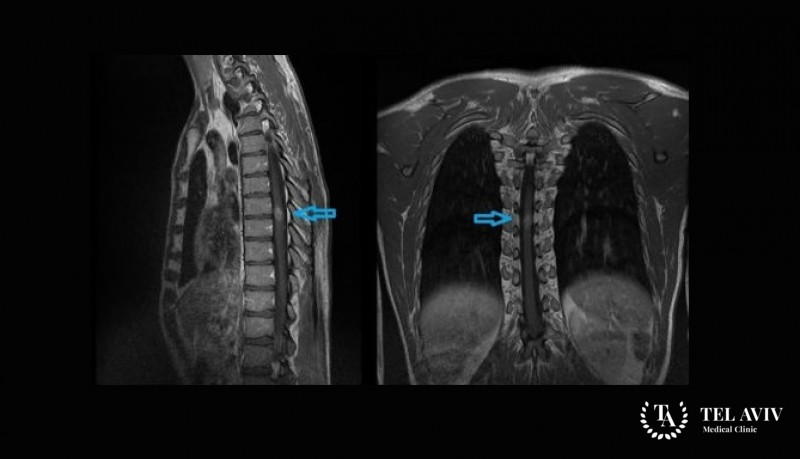

Для диагностики заболевания применяется компьютерная томография и магнитно-резонансная томография. Также больному делается биопсия, после чего проводится гистологическое исследование полученного образца.